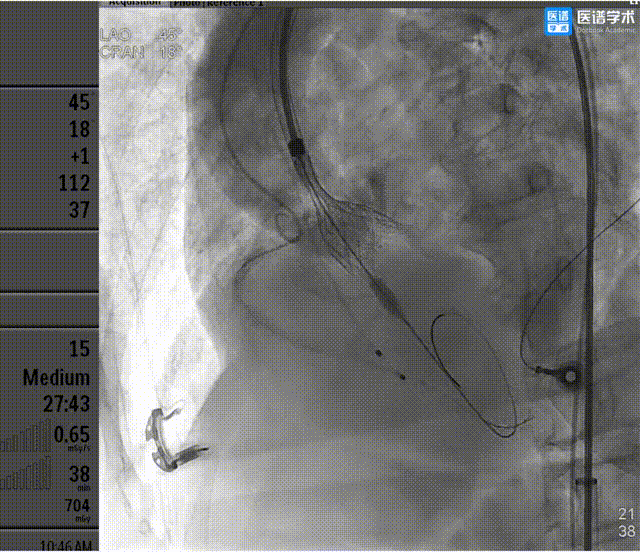

6、术中讨论决定行右冠保护措施,经右桡动脉送入6F JR3.5指引导管,行右侧冠脉造影,示患者右侧冠状动脉近段狭窄;

7、经6F JR3.5指引导管,送入3.5×28mm支架至RCA近段,预备行烟囱支架术;